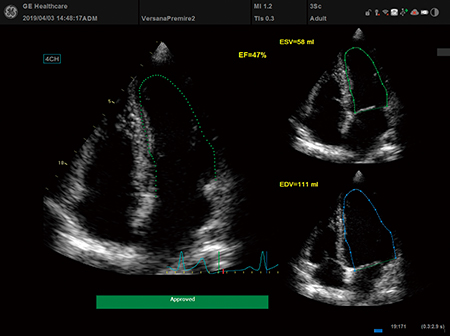

Auto EF - 心機能検査を,ルーティンに。

簡単に左心室の計測が可能。

保存画像からの計測もでき検査後に余裕をもって計測できます。

再現性が高く,定量的な評価に最適な機能です。